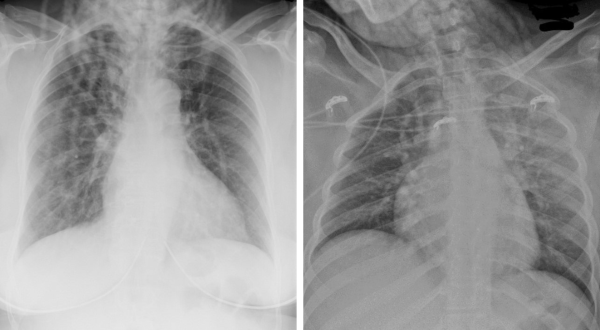

(Left) How a hairstyle of thick cornrows braided down presents on a chest x-ray; (right) how large braids present on a chest x-ray.

As Dr. Maresky explains, that’s a real problem. “Radiology is still a largely white profession, and many of us are biased in our thinking about what ‘normal hair’ should look like on radiologic imaging,” he says. “If an x-ray shows anything over the upper chest other than Caucasian hair, our first instinct is often that it’s abnormal, which can lead to a whole host of different—and incorrect—diagnoses.”

For example, a radiologist might decide that "locs" —which appear as a series of wavy lines on an x-ray—are evidence of tuberculosis or pneumothorax: two diagnoses that require serious, and potentially life-changing, treatment.